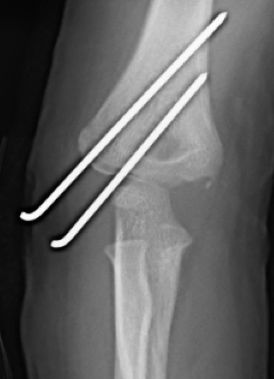

A menudo las radiografías convencionales, anteroposterior y lateral de codo, pueden infravalorar el desplazamiento real, por lo que se recomienda la realización de una proyección oblicua si fuera necesario, siendo ésta, la que mejor valora el desplazamiento. La línea de fractura va desde la superficie articular hasta la metáfisis distal del húmero. Las fracturas no desplazadas o mínimamente desplazadas (<2 mm) con integridad de la superficie articular se pueden tratar de forma conservadora mediante férula braquial y controles periódicos para valorar un posible desplazamiento secundario. Las fracturas desplazadas (>2 mm) precisan tratamiento quirúrgico. Si existe una afectación del cartílago articular, (evidenciado por RM o artrografía, está indicada la reducción abierta y estabilización con agujas de Kirschner (Figura 8). Una disección cuidadosa, respetando la zona posterior del cóndilo minimizará los riesgos de necrosis avascular del cóndilo humeral. Si la superficie articular está intacta, la reducción cerrada y estabilización con agujas de Kirschner es suficiente. La reducción anatómica de la superficie articular se realizará gracias a la visualización directa. En ocasiones, es difícil la reducción y la dorsiflexión de muñeca, relajando los músculos dorsiflexores, facilitará la reducción. La osteosíntesis se realizará con dos agujas de Kirschner lisas, con el punto de entrada posterior a la incisión y colocadas de forma paralela o divergente. A diferencia de las fracturas supracondíleas, en las que 3-4 semanas de inmovilización es suficiente, la inmovilización de las fracturas del cóndilo deben mantenerse por lo menos durante 4 semanas para evitar el riesgo de pseudoartrosis. Las agujas de Kirschner no se deben retirar hasta comprobar signos radiológicos de consolidación. Es importante informar a los padres de la posibilidad de aparición de una prominencia lateral, a menudo confundida con un cúbito varo, provocada por el hipercrecimiento óseo asociado a la atrofia de la musculatura. La rigidez articular es más frecuente que en las fracturas supracondíleas. La utilización de férulas dinámicas disminuye el riesgo de esta complicación.

Figura 8: a-d, Imagen radiografica de fractura del cóndilo lateral con desplazamiento articular. Tratamiento quirúrgico mediante reducción abierta y osteosíntesis.